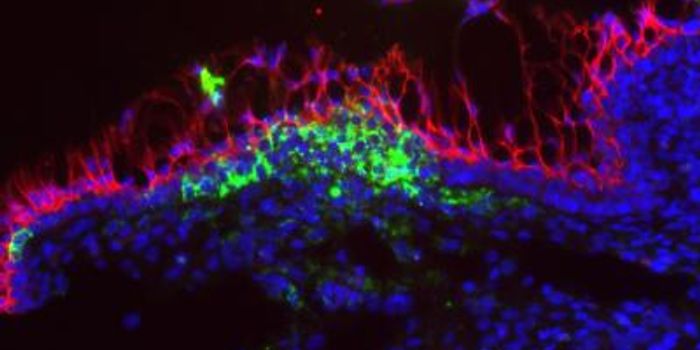

NOV 15, 2020NeuroscienceFor some time now, researchers have been aware that children and adults with autism tend to have different sensory syste ...